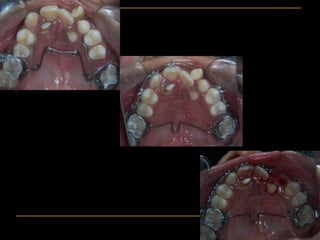

Upper Occlusal View

Post-Expansion Retention (Nance with

Extended Arm)

Occlusal View at 11/2 months

after Secondary Graft

ARCH EXPANSION